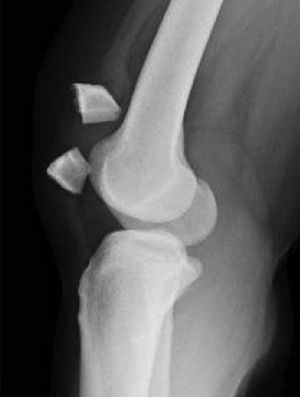

pycnodysostosis Pycnodysostosis is an autosomal recessive lysosomal storage disorder caused by a mutation in the gene encoding the enzyme cathepsin K. Features of pycnodysostosis include short stature and acro-osteolysis.

Classical example of pycnodysostosis, increased bone density, short stature (pyknic), frequent fractures and osteolysis of distal phalanges.